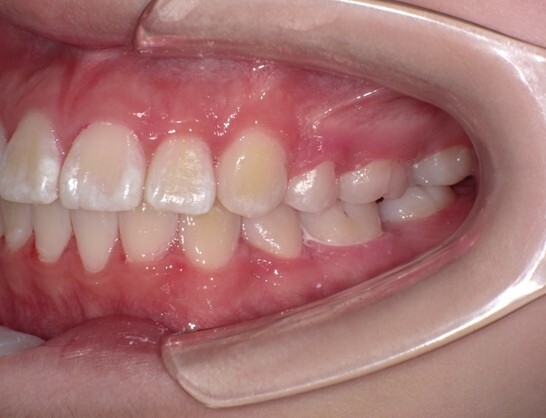

患者は13歳8か月の女子。主訴は左上に八重歯があること。上顎両側、下顎左側第一小臼歯を同時抜歯し、JET systemで治療を行ったところ動的治療期間は7か月であった。前歯部のトルクコントロール、上下顎正中の一致、咬合関係の改善が行われた。抜歯により誘発されたRAPを利用したJET systemでの治療は、治療期間の短縮に寄与し、患者QOLを向上させることが示唆された。